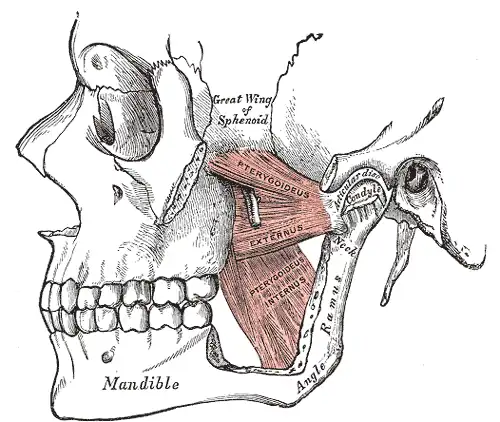

Its posterior surface is convex; its anterior surface has a depression for the attachment of the lateral pterygoid muscle.[1]

The Pterygoidei; the zygomatic arch and a portion of the ramus of the mandible have been removed.

The Pterygoidei; the zygomatic arch and a portion of the ramus of the mandible have been removed. -